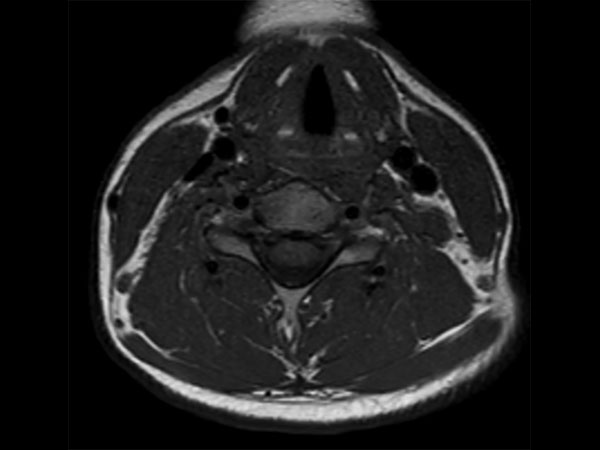

Comprehensive Cervical Spine imaging at 1.5T